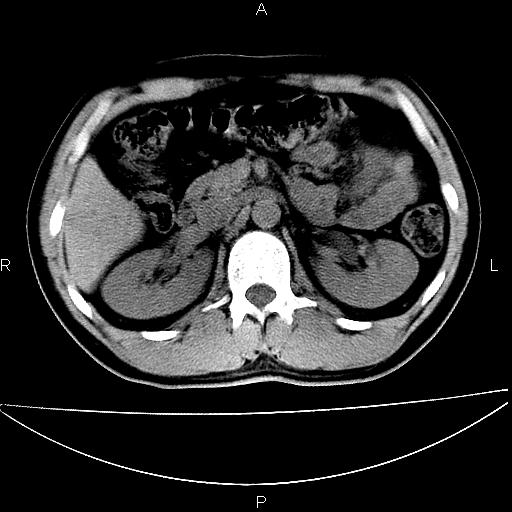

男 25岁 自述 尿频尿急,排尿困难20多天.无腰痛, b超说左肾盂轻度积水,左输尿管上端扩张.未见结石影. ct我看双侧肾盂轻度积水,双输尿管上端都扩张,大家看看能看见结石吗?

双肾轻度积水,双侧输尿管上段扩张(原因待查)。

双输尿管扩张下端未见高密度结石和输尿管晕轮征,不好说是结石.增强后如何?

双肾盂及双输尿上段轻度积水,双输尿管未见明显结石影。